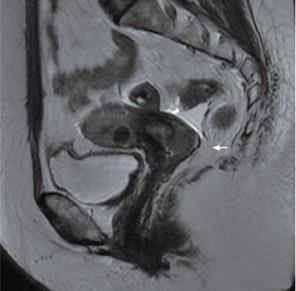

患者放疗前盆腔MRI图像示宫颈环周略长T2高信号 (箭头)